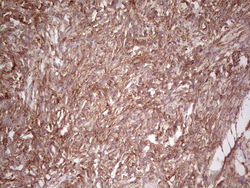

- Submitted by

- OriGene (provider)

- Main image

- Experimental details

- Immunohistochemical staining of paraffin-embedded Human prostate tissue within the normal limits using anti-WIBG mouse monoclonal antibody. (Heat-induced epitope retrieval by 1 mM EDTA in 10mM Tris, pH8.5, 120C for 3min, TA806496)

- Validation comment

- IHC